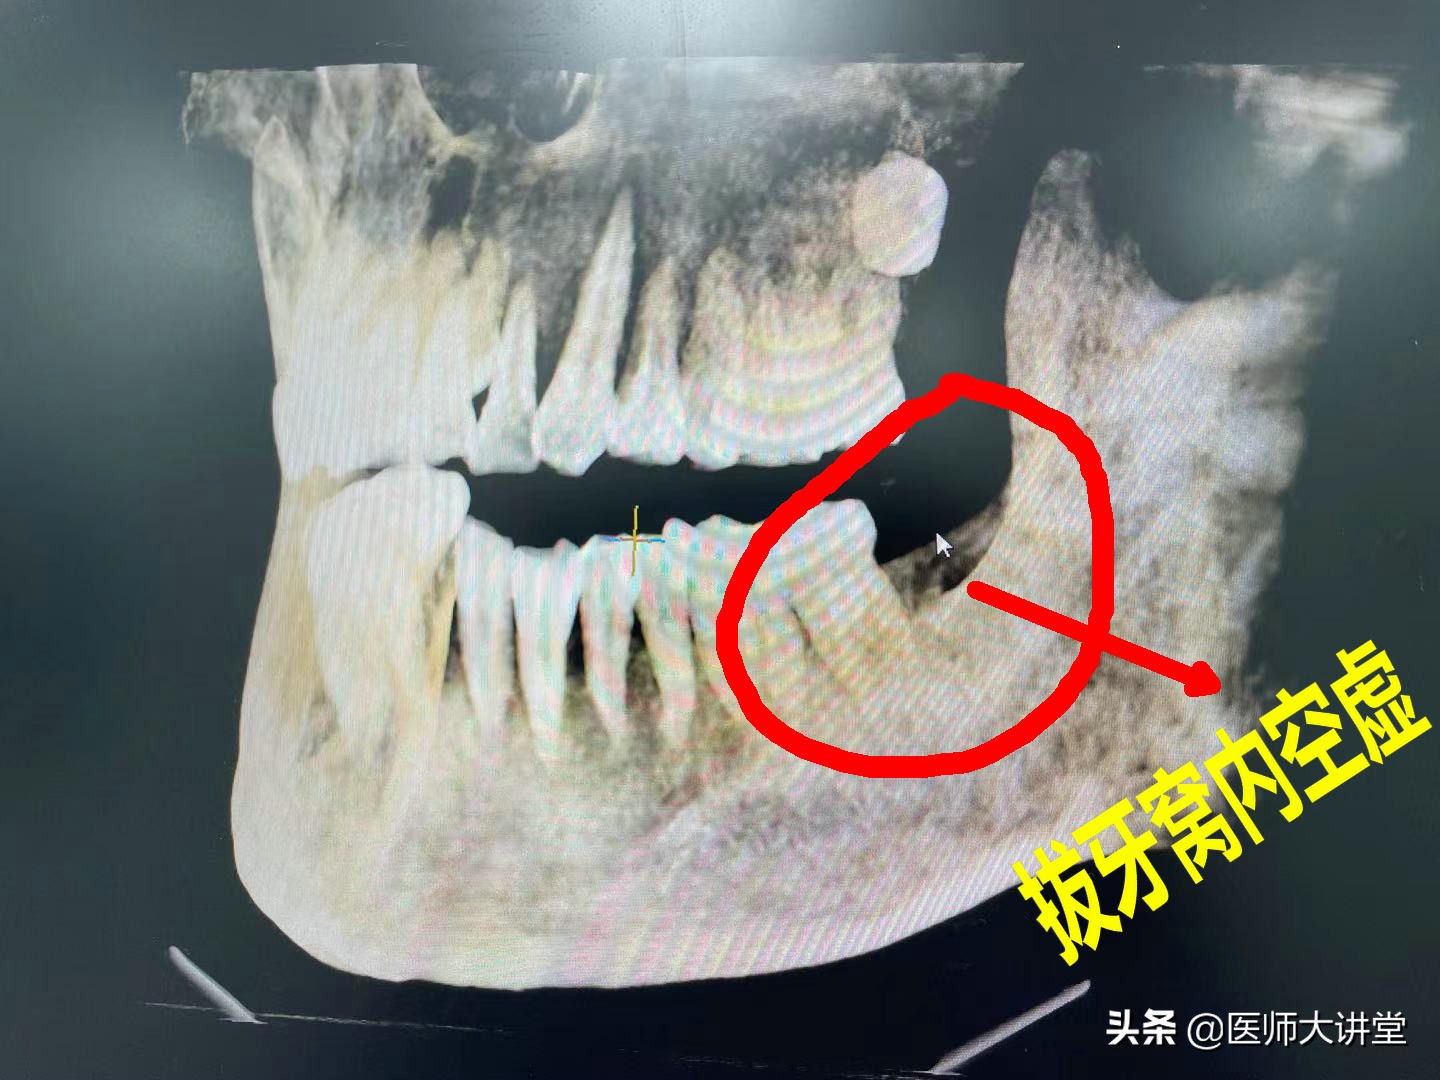

进行CBCT检查 第二次拍CT检查 初步诊断:非腐败型干槽症

第一次拍CT 拔牙窝内发现有不明物体。智齿拔的部位有一个洞(牙槽窝),口腔检查后发现一块豆牙皮把整个牙槽窝口封住。还有其他一些食物残渣。进一步查看里面碘仿药丸没有吸收。发现牙槽窝没有吸收愈合,呈空虚状。

洞内有没有血凝块,但是牙槽窝清爽没有发现分泌物。没有什么炎症表现和感染出现。没有什么特殊的味道。洞壁是颜色正常没有灰黑色的,触碰时不是很疼痛感觉。